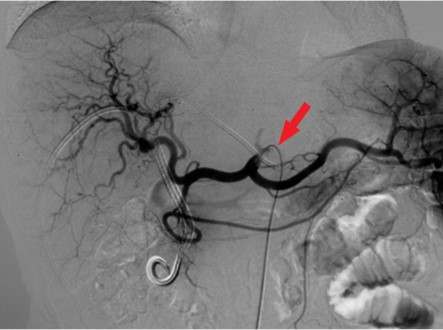

Материалы и методы. С 2017-го по 2021 г. в ФГБУ «РНЦРХТ им. академика А.М. Гранова» в протокол лечения нерезектабельной опухоли Клацкина с последующей трансплантацией печени было включено 6 пациентов. Неоадъювантное лечение включало эндобилиарную фотодинамическую терапию, регионарную и системную химиотерапию. Каждый метод применялся минимум трижды в течение четырех-пяти месяцев с радиологической оценкой и определением уровня Са19-9. Пациенты вносились в лист ожидания при снижении онкомаркера, отсутствии радиологических признаков прогрессии заболевания и без острого холангита. Реципиентам выполнялась лапароскопическая ревизия брюшной полости на предмет канцероматоза и оценка лимфоузлов печеночнодвенадцатиперстной связки со срочным морфологическим исследованием. При отсутствии внепеченочного распространения производилась трансплантация печени по классической методике с паракавальной, парааортальной и гепатодуоденальной лимфодиссекцией, билиодигестивным анастомозом на отключенной по Ру петле тонкой кишки. Операция выполнена трем пациентам, все из них – мужчины. Возраст колебался от 40 до 55 лет (средний – 48). Среднее время от начала лечения до трансплантации составило 9,3 месяца (от 6 до 14). Средний уровень Са19-9 на момент выполнения вмешательства составил 81,3 МЕ/мл (от 8 до 212).

Результаты. У трех пациентов, несмотря на лечение, отмечен рост уровня Са19-9 более чем в два раза в среднем за четыре месяца. У двух из них выявлена прогрессия заболевания согласно данным компьютерной томографии по RECIST. У одного пациента выявлен канцероматоз при диагностической лапароскопии. У трех пациентов Са19-9 снизился более чем в четыре раза. У двух из этих пациентов радиологически подтверждена стабилизация заболевания, у одного – частичный ответ. Один пациент умер через три года после трансплантации от сепсиса в исходе вторичного билиарного цирроза и билиарных абсцессов без признаков прогрессирования. Два пациента живы по настоящее время на протяжении 6 и 21 месяцев без признаков прогрессирования опухоли.